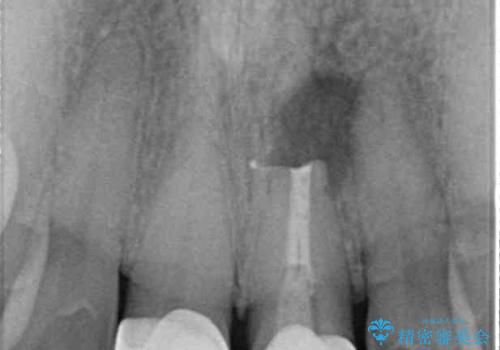

半年強経過した際のレントゲン写真では、処置前のレントゲン透過像と切除した歯根部分がしっかりと歯槽骨となっている様子が認められました。